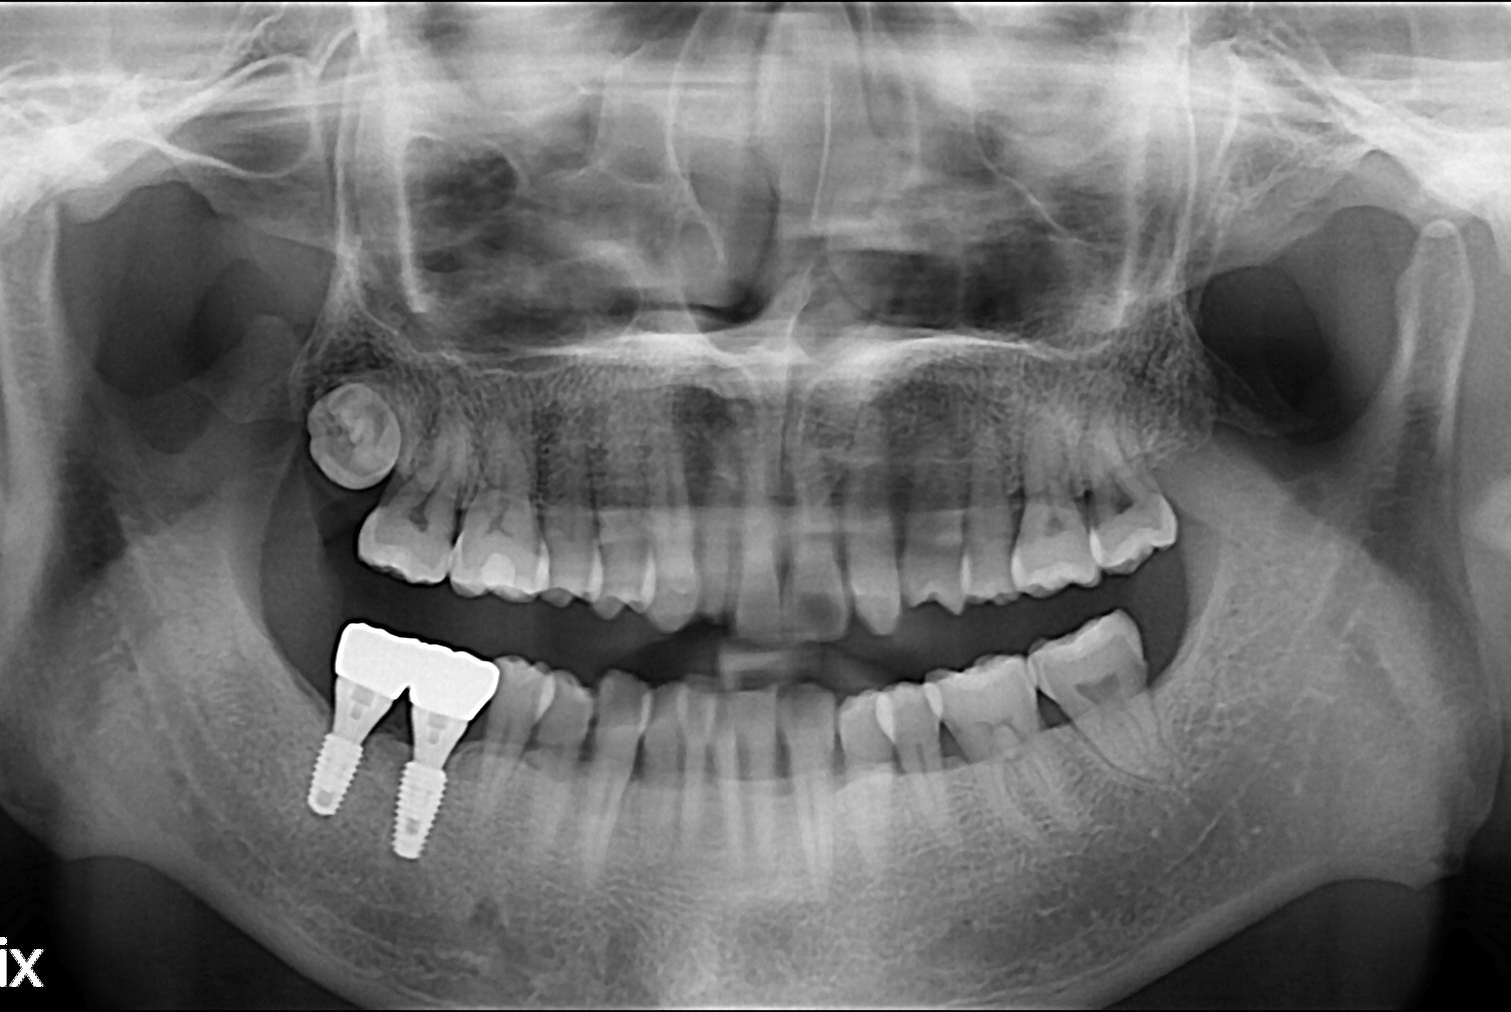

치료전 : 2017-10-19

치료후 : 2017-12-14

세종치과는 많은 환자와 다양한 케이스를 바탕으로 항상 편안한 임플란트 수술을 제공하고자 노력하고,

오래동안 튼튼히 쓸 수 있는 임플란트 수술을 가장 큰 목표로 삼고 있습니다